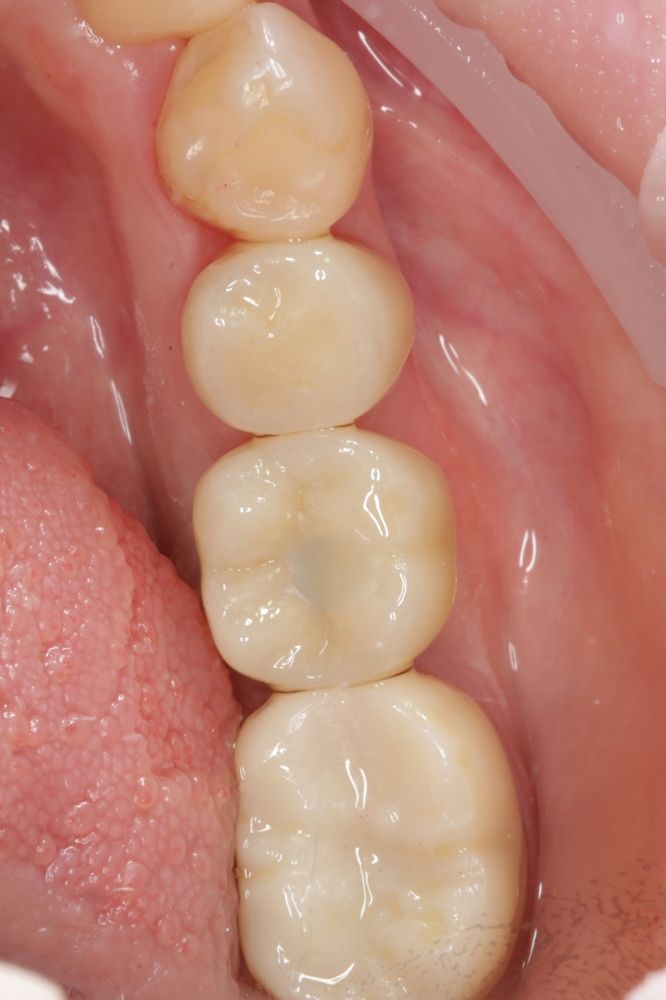

Имплантация жевательных зубов,

это самая востребованная операция.

Анна Анатольевна Кушнарева

хирург - имплантолог

фото коронок